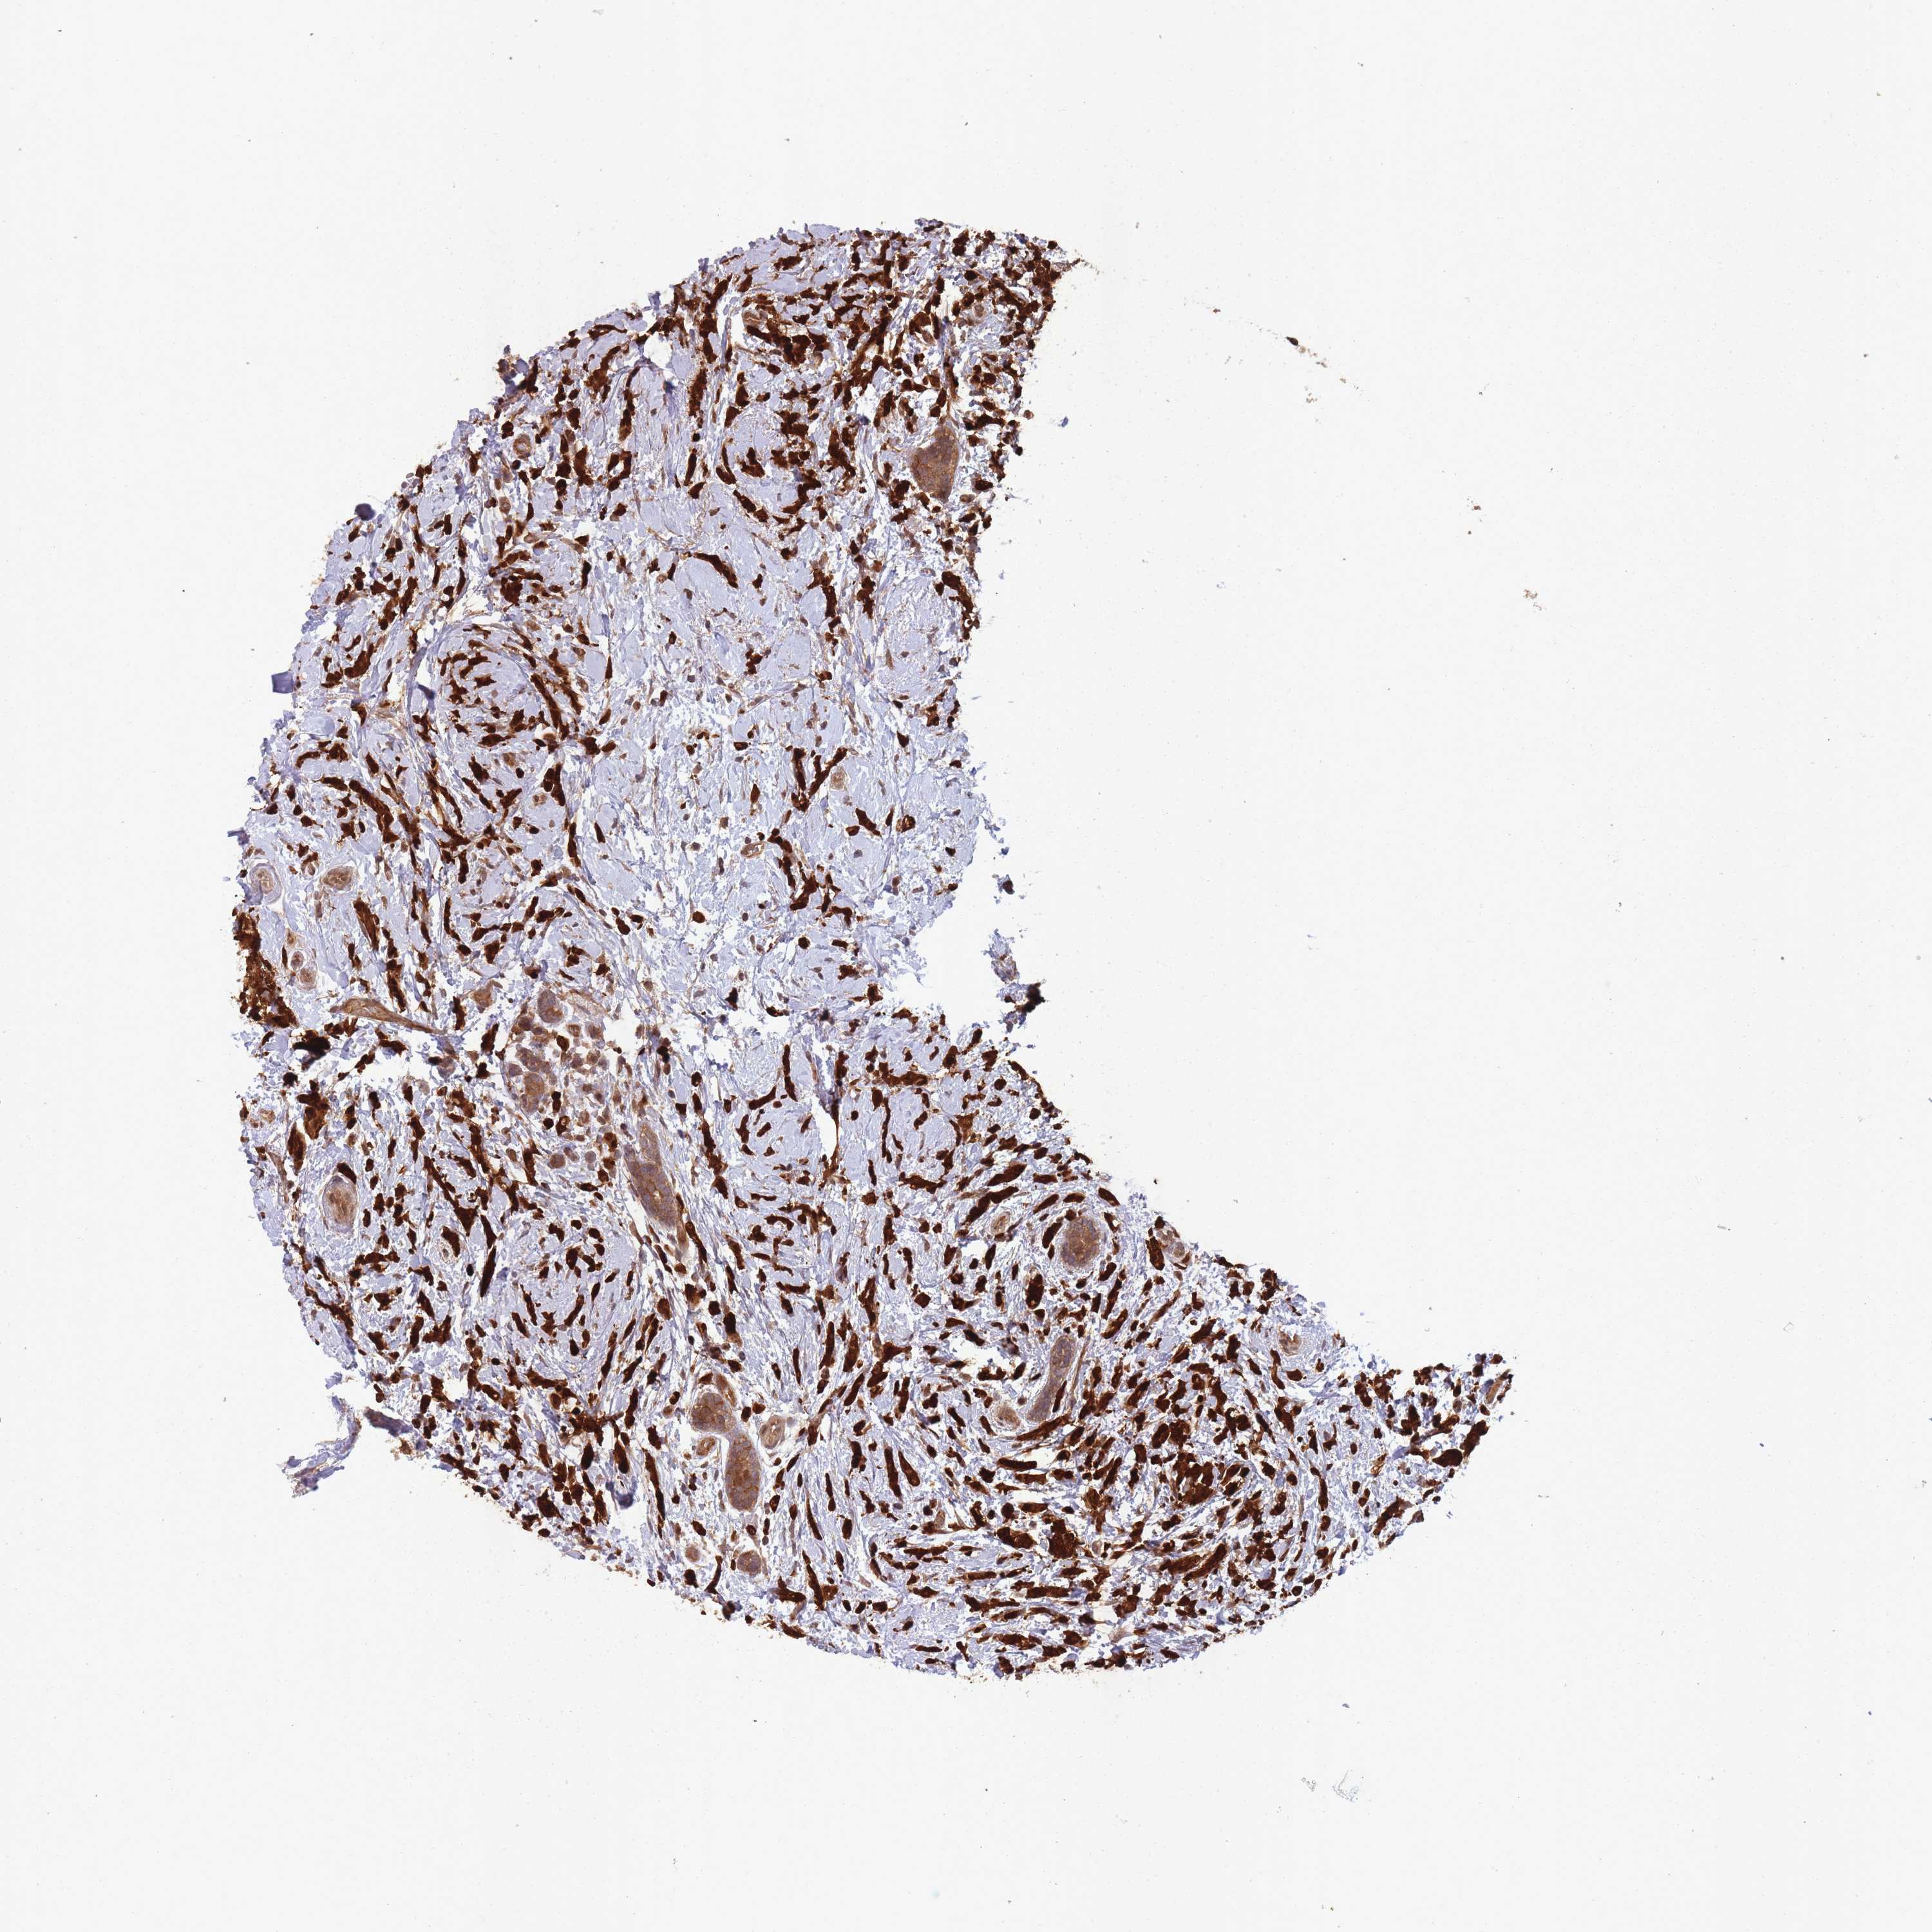

BRCA TCGA BRCA VALIDATION PROTEIN EXPRESSION

ANTIBODIES

AND

VALIDATION